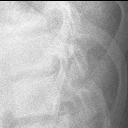

椎体骨折

椎体骨折2